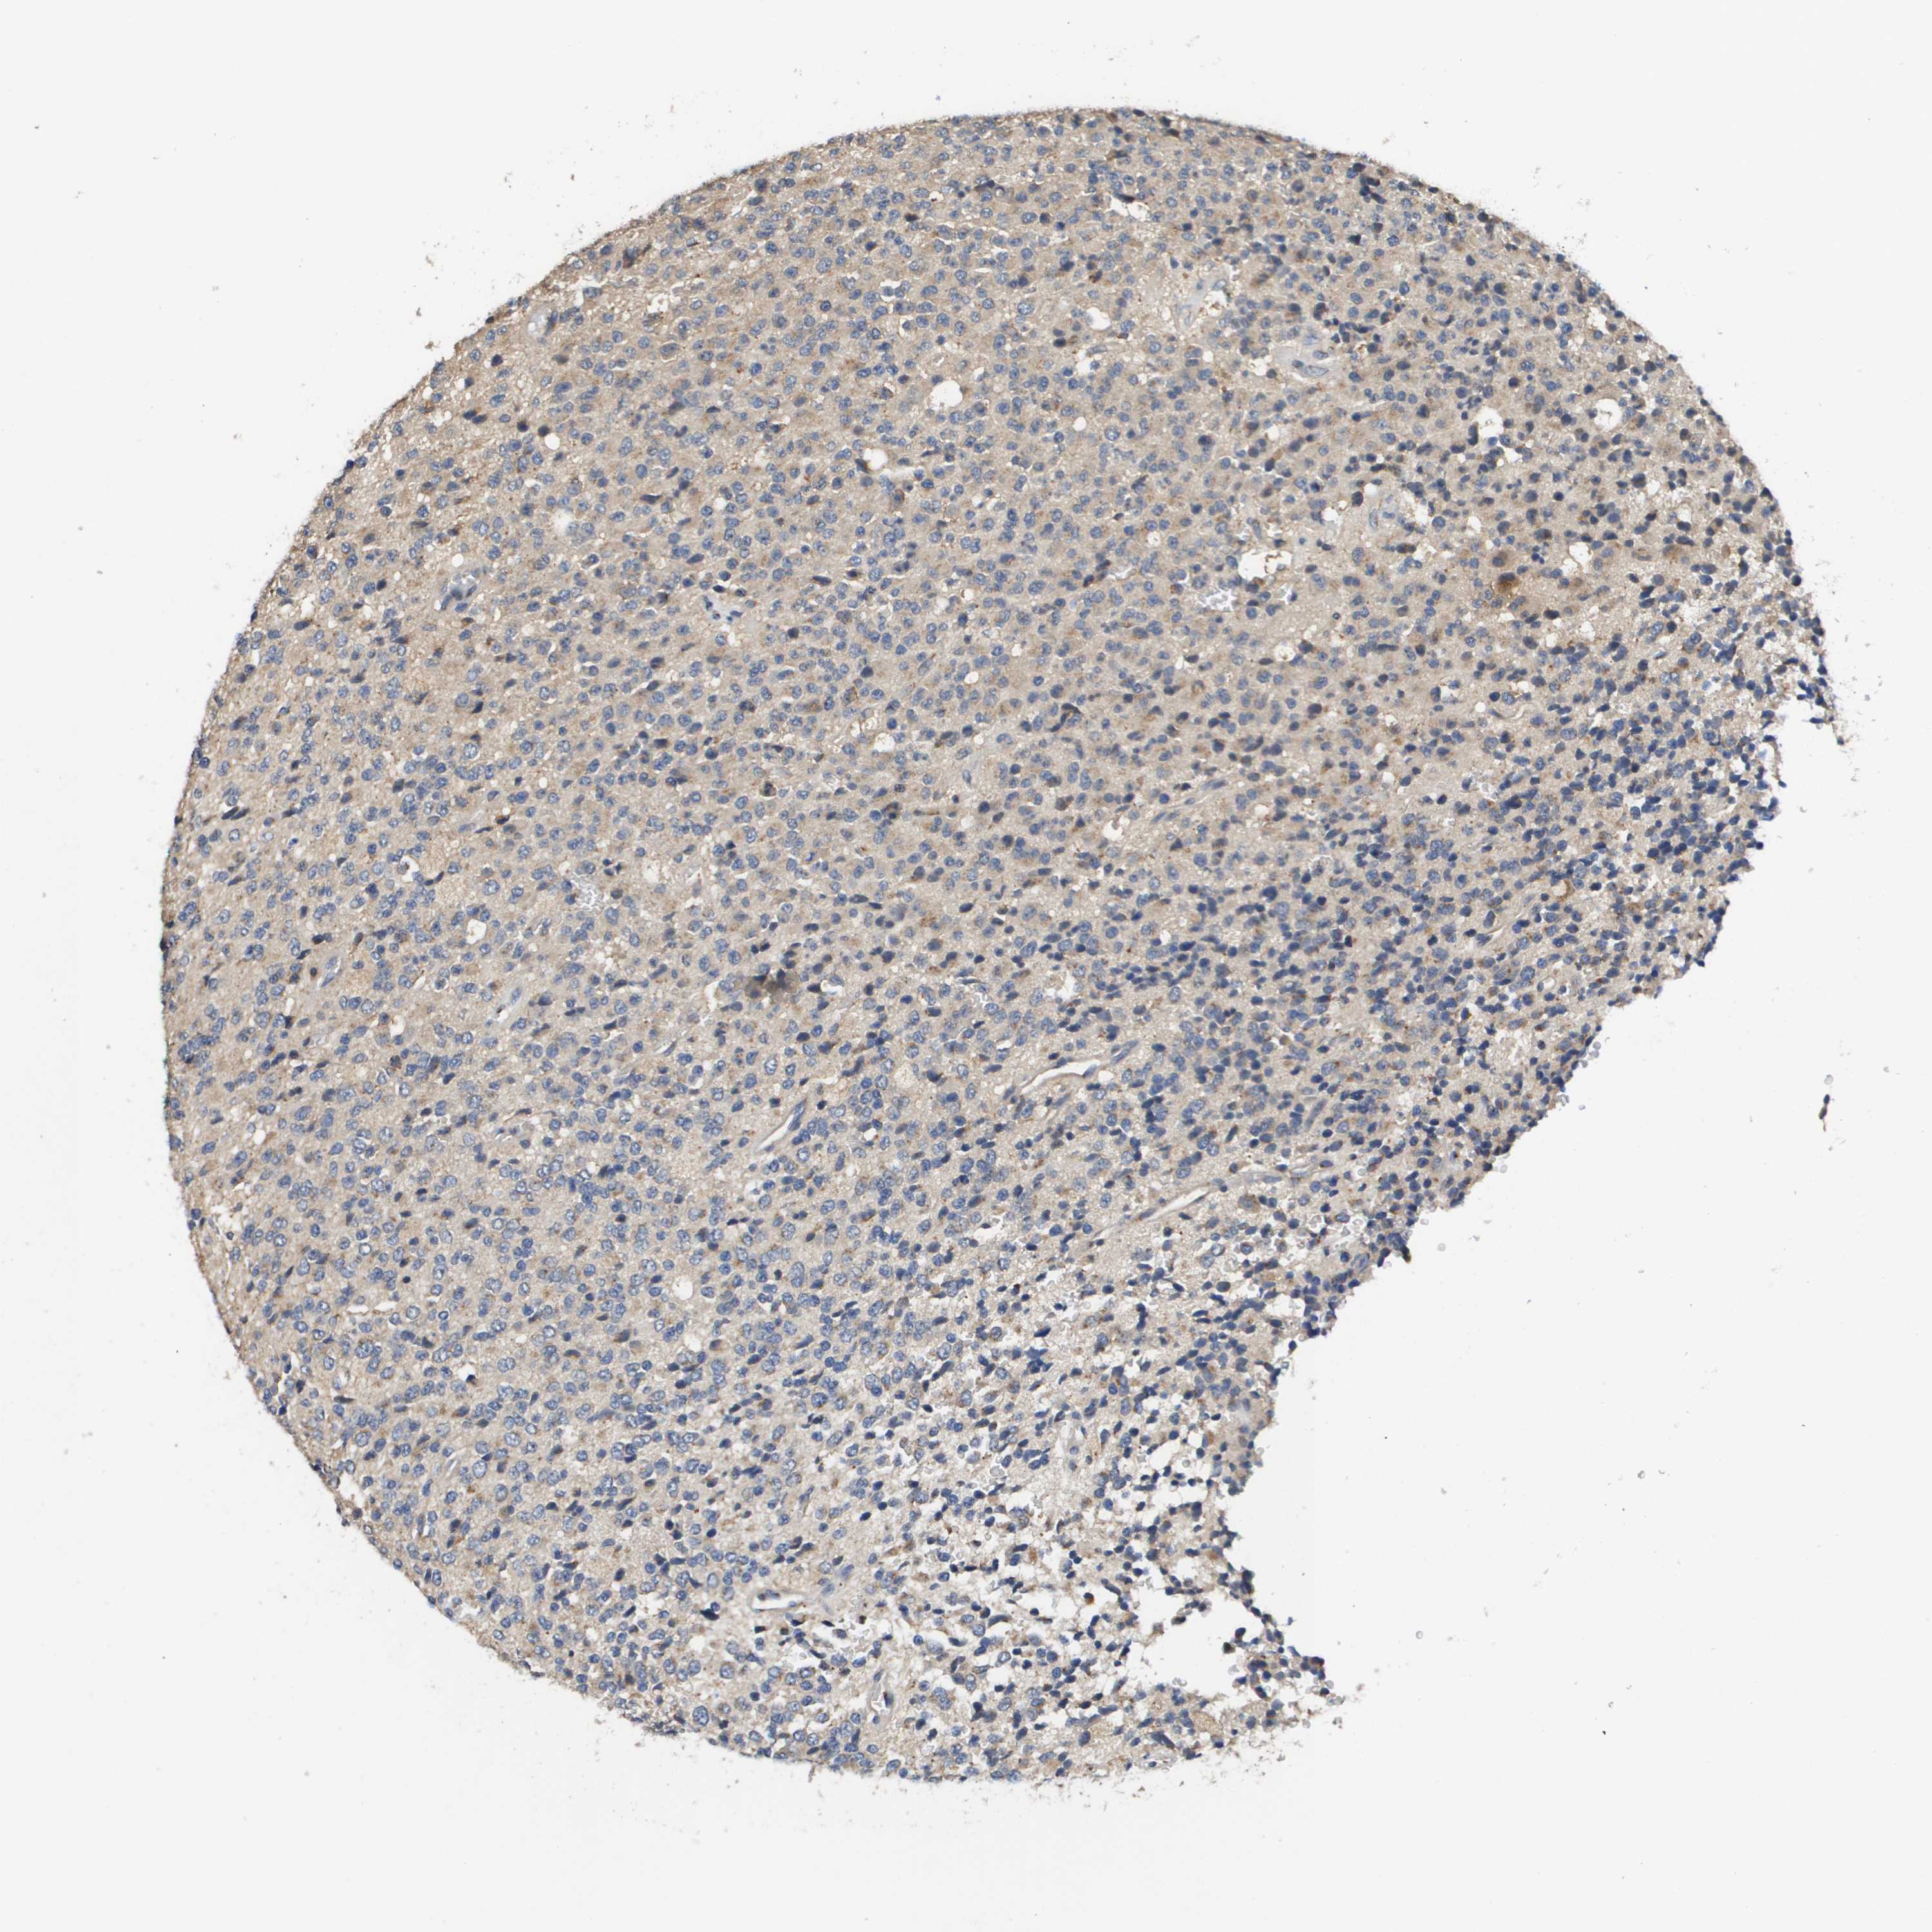

GLIOMA - Protein expressioni

A mouse-over function shows sample information and annotation data. Click on an image to view it in a full screen mode. Samples can be filtered based on level of antibody staining by selecting one or several of the following categories: high, medium, low and not detected. The assay and annotation is described here.

Note that samples used for immunohistochemistry by the Human Protein Atlas do not correspond to samples in the TCGA dataset.

Antibody stainingi

Antibody staining in the annotated cell types in the current human tissue is reported as not detected, low, medium, or high, based on conventional immunohistochemistry profiling in selected tissues. This score is based on the combination of the staining intensity and fraction of stained cells.

Each image is clickable and will lead to virtual microscopy that enables deeper exploration of all samples and also displays staining intensity scores, fraction scores and subcellular localization as well as patient and tissue information for each sample.

Antibody HPA006277

Antibody HPA006507

Antibody CAB017027

Staining

High

Medium

Low

Not detected

Intensity

Strong

Moderate

Weak

Negative

Quantity

>75%

75%-25%

<25%

None

Location

Nuclear

Cytoplasmic/membranous

Cytoplasmic/membranous,nuclear

Glioma, malignant, Low grade

Glioma, malignant, High grade